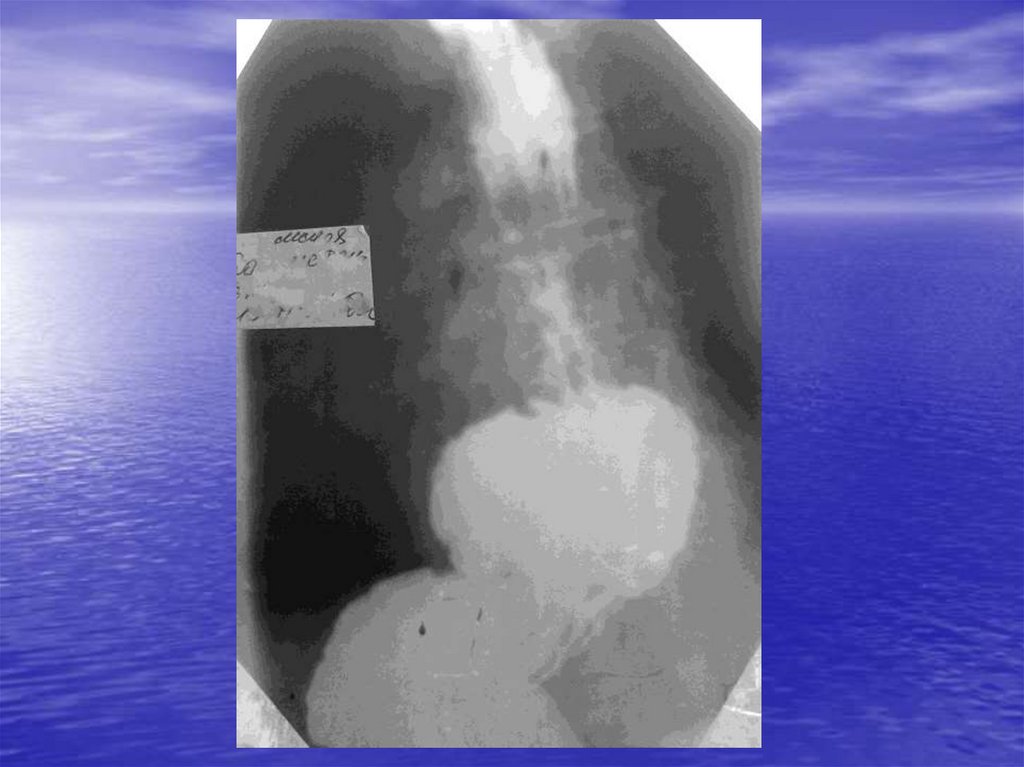

А) Ахалазия кардии

Б) Недостаточность кардии

В) Рефлюкс эзофагит (пептический эзофагит, коррозионный

эзофагит).